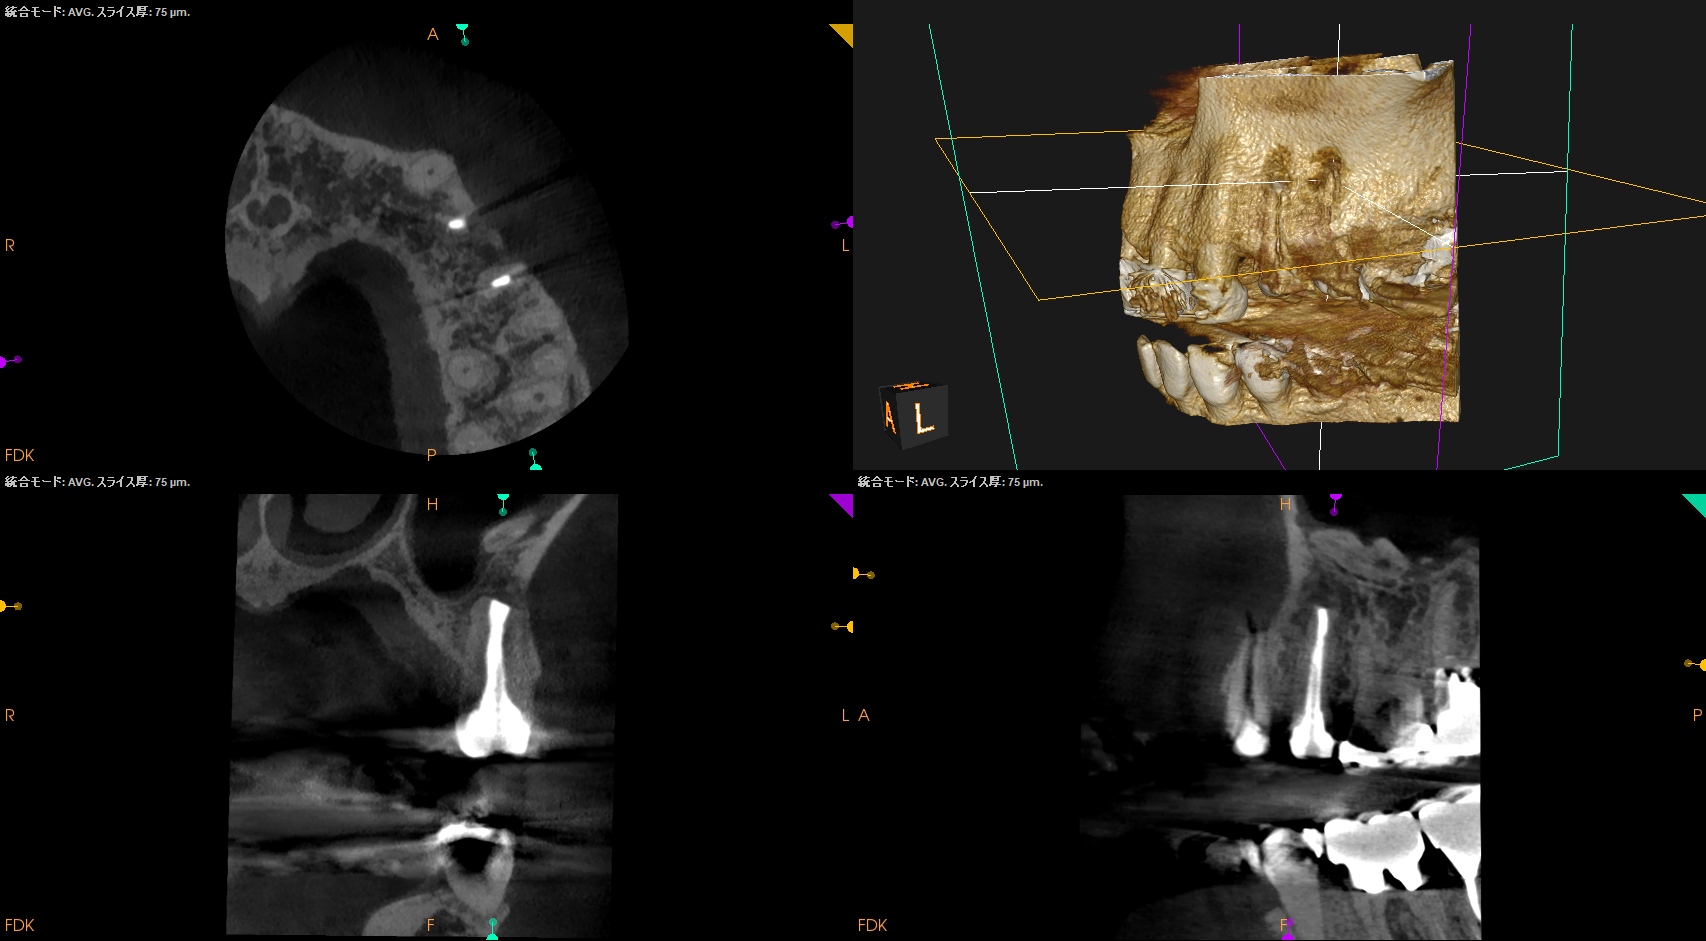

#12,13 Apicoectomy 6M recall(2026.3.31)

#12

#13

術前・直後と比較した。

最終補綴はOKである。